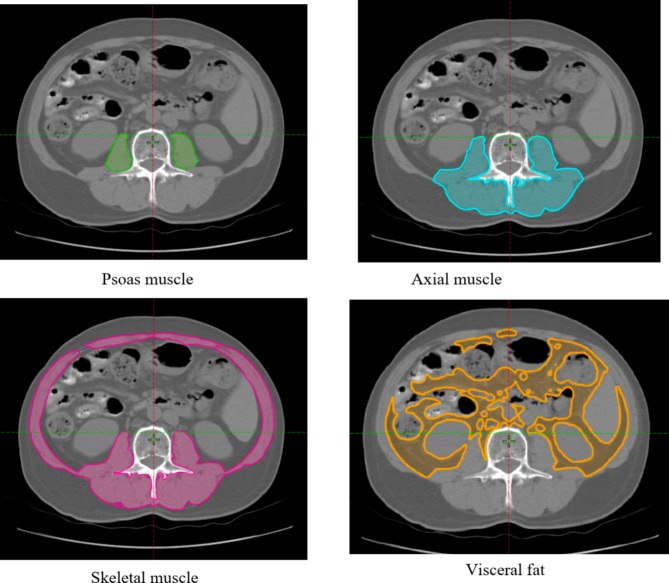

本研究旨在探讨肌肉浸润性膀胱癌(MIBC)根治性膀胱切除术(RC)后180天内,肌骨增生症、肌肉减少症和围手术期血清生物标志物作为主要并发症的独立预测因素的作用。我们回顾性分析了2013年至2023年间在一家机构接受RC治疗的127例MIBC患者。术前身体组成评估采用CT扫描在L3椎体水平测量腰肌密度(PMD),骨骼肌密度(SMD),轴向肌密度(AMD)和肌肉指数。新的炎症和营养指标,包括术后24小时内的血清氯化物水平,也进行了评估。主要并发症定义为Clavien-Dindo分级≥3级。进行多变量分析以确定术后并发症的独立预测因素。在队列中,30.7%的患者在90天内出现严重并发症,36.2%的患者在180天内出现严重并发症。脓毒症是最常见的主要并发症(241个并发症中有19个,7.9%)。观察期内死亡10例。肌骨化症(p = 0.002)和术后血清氯化物水平(p = 0.002)

This study aimed to investigate the role of myosteatosis, sarcopenia, and perioperative serum biomarkers as independent predictors of major complications within 180 days following radical cystectomy (RC) for muscle-invasive bladder cancer (MIBC). We retrospectively analyzed of 127 MIBC patients who underwent RC between 2013 and 2023 at a single institution. Preoperative body composition was assessed using CT scans at the L3 vertebral level to measure psoas muscle density (PMD), skeletal muscle density (SMD), axial muscle density (AMD), and muscle indices. Novel inflammatory and nutritional markers, including serum chloride levels within 24 h post-surgery, were also evaluated. Major complications were defined as Clavien-Dindo grade ≥ 3. Multivariate analysis was performed to identify independent predictors of postoperative complications. Among the cohort, 30.7% of patients experienced major complications within 90 days, and 36.2% within 180 days. Sepsis was the most common major complication (19 of 241 complications, 7.9%). Ten patients died during the observation period. Myosteatosis (p = 0.002) and postoperative serum chloride levels (p < 0.001) were significant independent predictors of 180-day major complications. Patients with low PMD had an adjusted odds ratio (OR) of 3.959 for developing major complications, while increased serum chloride levels were associated with a reduced risk of complications (OR = 0.985). Multivariate analysis reveals associations between myosteatosis, aging, and anemia. Myosteatosis and perioperative serum chloride levels are significant predictors of major complications after RC for MIBC. Incorporating body composition analysis and early serum chloride monitoring into perioperative care may improve risk stratification and patient outcomes following RC.